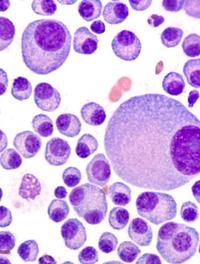

Les taux de guérison des enfants, adolescents et jeunes adultes atteints de leucémie lymphoblastique aiguë (LLA) se sont beaucoup améliorés [...]

Tisagenlecleucel est un traitement par cellules T porteuses d’un récepteur antigénique chimérique (CAR) qui cible le CD19. Ce traitement [...]